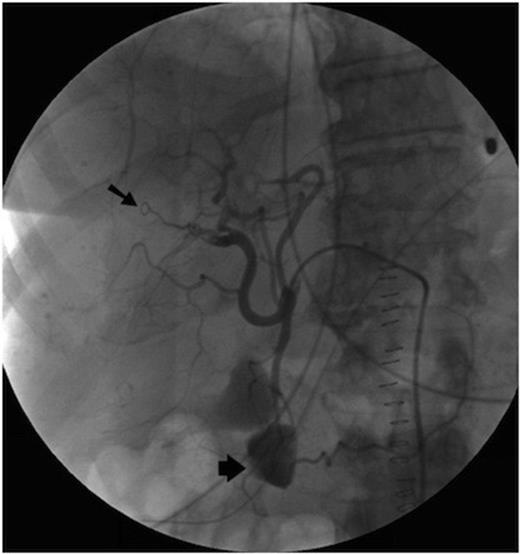

Initially, selective embolisation of the anterior right hepatic artery was performed using small coils (COOK UK) and small particles of grated gelatin sponge soaked in 0.5ml of 5% Ethanolamine. However this proved to be ineffective (Figure 2), and so the posterior branch of the right hepatic artery was embolised, successfully controlling the haemobilia. The left hepatic artery was spared.